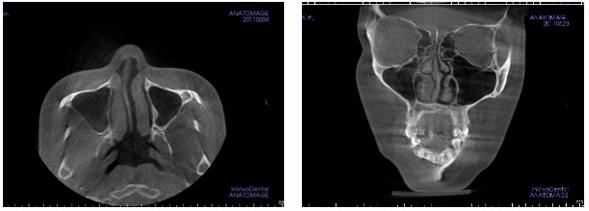

4、利用3DCT的鼻塞手术

利用鼻内CT映像掌握鼻塞的原因,如有必要,在隆鼻手术里,同时实行鼻中隔弯曲矫正手术或下鼻甲介矫正手术。